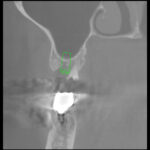

まず、かみあわせの精査のためのキャディアックスとセファロ分析をさせていただき歯周病改善のための予防プログラムにはいり、左右の下の奥歯にはインプラントを2本づつ埋入させていただきました。すべての歯にプロビショナルレスト(治療用の仮の歯)を装着させていただき。咬み合わせの安定歯肉の腫れ出血がない状態をしみや痛みがない状態を確認した後に、すべてプロセラで歯を作らせていただきました。

プロセラを使わせていただいたため、歯の切削量を少なくすることができ、結果としてほとんど神経を残してかぶせることができました。また歯に生じたヒビや穴は奥歯の不足による負担過重と歯ぎしりによるものでしたからこのような歯は内部の神経が自然に細くなっておりこのことがまた神経を残してもしみない要件の一つでした。